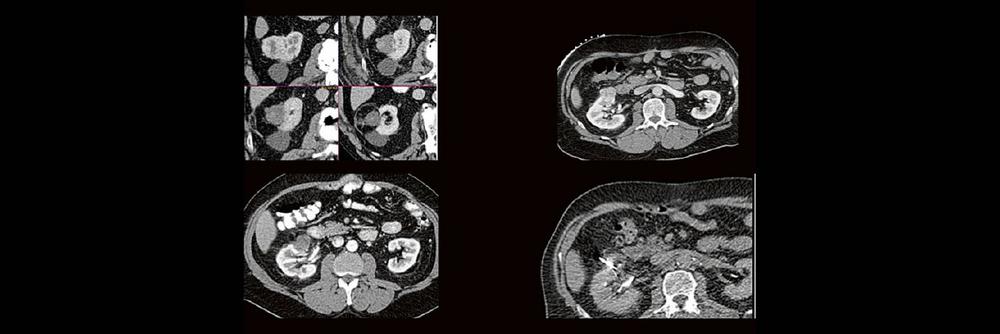

Professor Dr. med. Marc Brockmann WEITERENTWICKLUNGEN VON KOPF BIS FUSS BEIM VC Oberstarzt Dr. med. Stephan Waldeck DEEP-LEARNING-REKONSTRUKTION IN DER NEURORADIOLOGIE Die CT ist ein essentielles Routine-Verfahren in der Neuroradiologie. Bei steigender Bildqualität konnte die Röntgendosis mit neuen Technologien in der letzten Dekade deutlich gesenkt werden, was für die zielgerichtete und möglichst schonende Behandlung von…